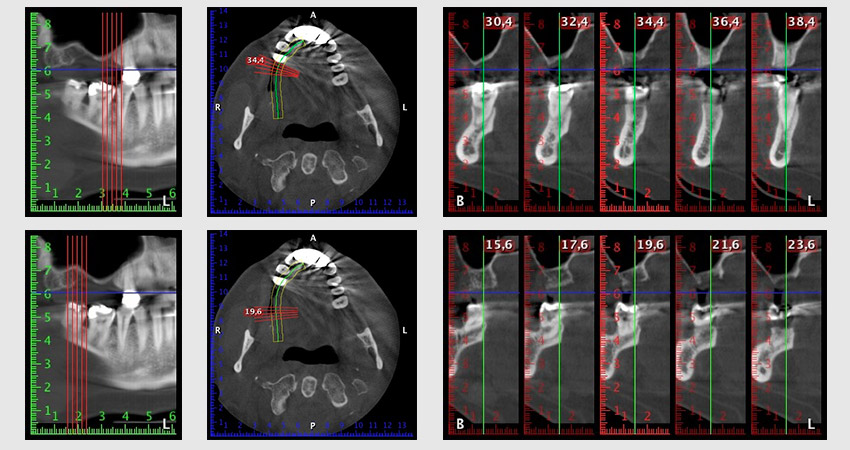

About six months after teeth 16 and 14 were extracted, a digital volume tomography (DVT, Planmeca) examination was performed for planning and risk minimization purposes. It clearly showed that the bone had not regenerated to the desired volume (Fig. 2 to 7).

To restrict the augmentation to region 14, and in consultation with the patient, it was planned that implant 16 would be placed, inclined, in the dorso-cranial direction (Fig. 8).